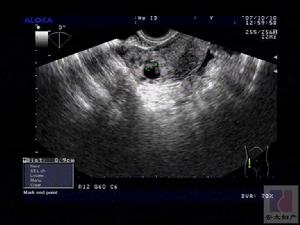

腹腔镜检查颈息肉形成的原因可能与炎症内分泌紊乱特别是雌激素水平过高有关。比如长期炎症会容易导致宫颈息肉。宫颈息肉有以下检查方法:

子宫息肉BBT自凝技术治疗:它主要是通过B超的动态观察和仪器自动控制,治疗源经过阴道、宫颈等自然腔道,准确定点地介入到人体的病变部位,自动精确地控制治疗功率、时间和治疗范围,射频使病变局部组织产生生物高热效应。然后使病变组织发生凝固、变性和坏死,使病变组织得以消融,最后被正常组织吸收和自动排除,从而达到治疗的目的。 医学百科网 | YxBaike.Com